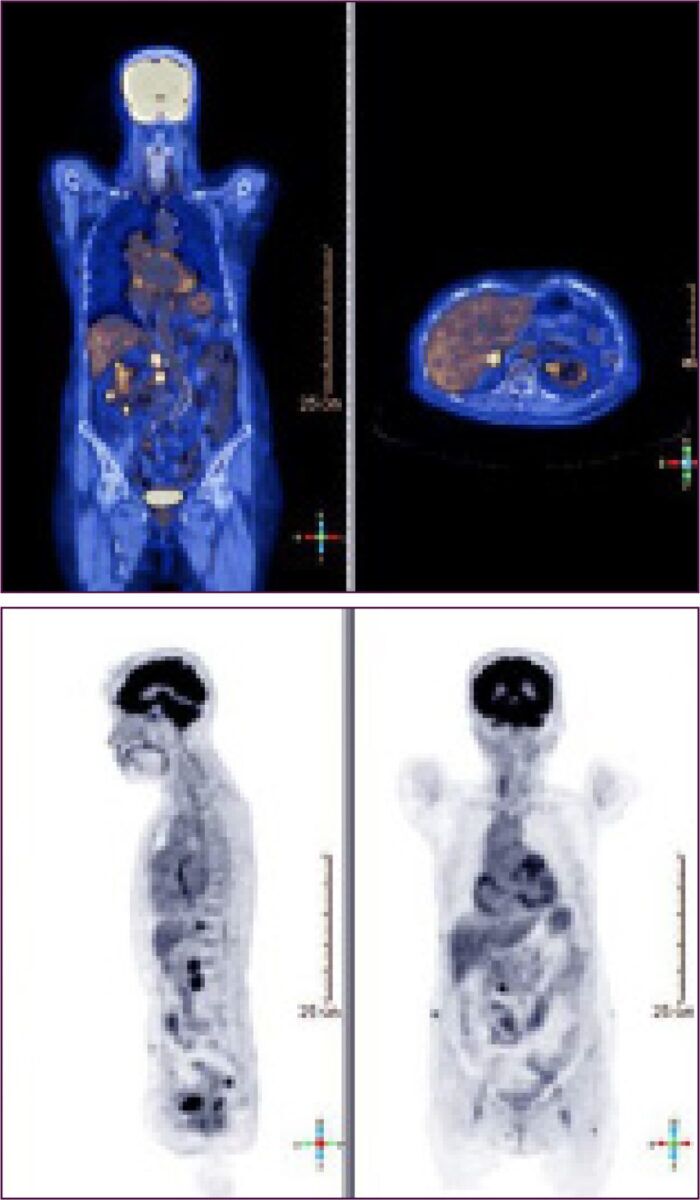

Molecular imaging expertise

Advances in molecular imaging enable the ability to measure functional changes in tumor microenvironments. Clario supports a full range of molecular imaging modalities used to identify, stage, and monitor various cancers.